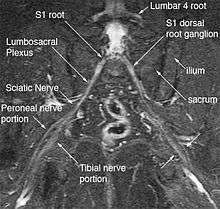

The most significant impact of magnetic resonance neurography is on the evaluation of the large proximal nerve elements such as the brachial plexus (the nerves between the cervical spine and the underarm that innervate shoulder, arm and hand),[9] the lumbosacral plexus (nerves between the lumbosacral spine and legs), the sciatic nerve in the pelvis,[10] as well as other nerves such as the pudendal nerve[11] that follow deep or complex courses.

Neurography has also been helpful for improving image diagnosis in spine disorders. It can help identify which spinal nerve is actually irritated as a supplement to routine spinal MRI. Standard spinal MRI only demonstrates the anatomy and numerous disk bulges, bone spurs or stenoses that may or may not actually cause nerve impingement symptoms.[12][13]

Use of magnetic resonance neurography is increasing in neurology and neurosurgery as the implications of its value in diagnosing various causes of sciatica becomes more widespread.[24][25] There are 1.5 million lumbar MRI scans performed in the US each year for sciatica, leading to surgery for a herniated disk in about 300,000 patients per year. Of these, about 100,000 surgeries fail. Therefore, there is successful treatment for sciatica in just 200,000 and failure of diagnosis or treatment in up to 1.3 million annually in the US alone. The success rate of the paradigm of lumbar MRI and disk resection for treatment of sciatica is therefore about 15%(Filler 2005). Neurography has been applied increasingly to evaluate the distal nerve roots, lumbo-sacral plexus and proximal sciatic nerve in the pelvis and thigh to find other causes of sciatica. It is increasingly important for brachial plexus imaging and for the diagnosis of thoracic outlet syndrome.[26] Research and development in the clinical use of diagnostic neurography has taken place at Johns Hopkins, the Mayo Clinic, UCLA, UCSF, Harvard, the University of Washington in Seattle, University of London, and Oxford University (see references below) as well as through the Neurography Institute. Recent patent litigation concerning MR Neurography has led some unlicensed centers to discontinue offering the technique. Courses have been offered for radiologists at the annual meetings of the Radiological Society of North America (RSNA), and at the International Society for Magnetic Resonance in Medicine and for surgeons at the annual meetings of the American Association of Neurological Surgeons and the Congress of Neurological Surgeons. The use of imaging for diagnosis of nerve disorders represents a change from the way most physicians were trained to practice over the past several decades, as older routine tests fail to identify the diagnosis for nerve related disorders. The New England Journal of Medicine in July 2009 published a report on whole body neurography using a diffusion based neurography technique.[27] In 2010, RadioGraphics - a publication of the Radiological Society of North America that serves to provide continuing medical education to radiologists - published an article series taking the position that Neurography has an important role in the evaluation of entrapment neuropathies.[28]